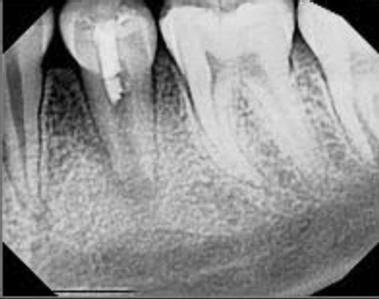

Cover: It’s a tricky situation. Patient with partial denture

Technique for extracting tooth or root tip from underneath fixed partial denture emphasizes use of magnification from dental loupes or dental surgical operating microscope for precision when performing technique-sensitive procedure. Case report.